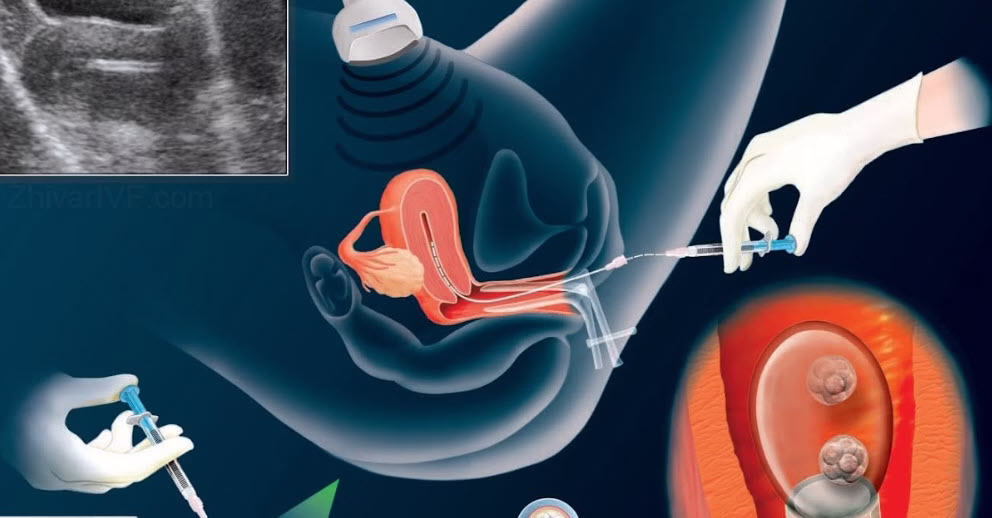

فرایند انتقال جنین یکی از مراحل نهایی درمان ناباروری است که در آن , جنین های آماده و سالم به کمک ابزار ظریف و مخصوصی به داخل رحم منتقل می شوند این مرحله بدون نیاز به بیهوشی و معمولاً بدون درد انجام می شود و تنها چند دقیقه زمان می برد ، رعایت دقیق توصیه های پزشکی پیش و پس از انتقال نقش مهمی در افزایش احتمال موفقیت درمان دارد .

انتقال جنین عملی سریع و بدون درد است که معمولاً نیازی به آرام بخش یا بیهوشی ندارد . بااین حال بهتر است در روز انتقال به دلیل نیاز به بیهوشی احتمالی , بیمار ناشتا بوده و آنتی بیوتیک نیز استفاده نکند . همچنین در روز انتقال , مثانه بیمار باید پر باشد; زیرا به وضوح بهتر تصویر سونوگرافی در زمان انتقال کمک می کند .

در زمان انتقال , بیمار به کمک پرستار در شرایط استریل به اتاق عمل منتقل شده و در وضعیت خوابیده به پشت قرار می گیرد دهانه رحم با استفاده از محیط کشت آزمایشگاه شستشو داده شده و رحم برای مشاهده مسیر حرکت کاتتر انتقال جنین توسط پروب شکمی دستگاه سونوگرافی بررسی می شود .

در همین زمان در آزمایشگاه , متخصص جنین شناسی , جنین هایی را که از پیش , کیفیت آنها بررسی شده و شرایط مساعد و مطلوب برای انتقال دارند , از انکوباتور خارج کرده , نام و نام خانوادگی مادر را بر روی ظرف کشت جنین با نام و نام خانوادگی بیمار بستری شده تطبیق داده و توسط شاهدین (دستیاران جنین شناسی و اتاق عمل) تایید میکند . جنین های منتخب با اعلام آمادگی پزشک متخصص درون کاتتر بارگذاری شده و به اتاق عمل منتقل می شوند .

جنین های بارگذاری شده از طریق دهانه رحم به بالای رحم هدایت و رها می شوند . با توجه به تغییر طول فضای آندومتر در هر بیمار , بهترین مکان برای رهاسازی جنین براساس عمق حفره رحم تعیین می شود . میزان بارداری با فاصله قطره محیط کشت حاوی جنین از سطح فوندوس در ارتباط بوده به طوریکه بیشترین میزان بارداری در فاصله یک سانتی متری قطره محیط کشت از این قسمت گزارش شده است (تصویر زیر) .

پیش از آن که خاتمه عمل اعلام شود , جنین شناس کاتتر را سریعاً در آزمایشگاه بررسی میکند تا مطمئن شود جنینی در داخل کاتتر باقی نمانده است . با اعلام تایید انتقال موفق از سوی جنین شناس , بیمار پس از یک استراحت کوتاه می تواند ترخیص شود . کل این فرایند از ابتدا تا انتها 10 تا 15 دقیقه طول می کشد .